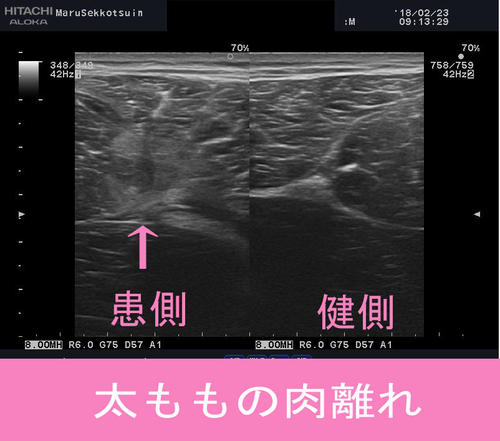

昨日から、また「ふとももの肉離れ」、

「ふくらはぎの肉離れ」の患者さまが急増中。

低気温時、外部環境により、筋肉は柔軟性をを失い、

筋膜や筋繊維の断裂などの損傷を起しやすい状態となっております。

そこに大腿四頭筋(ふとももの前の筋肉)を中心に、

周囲関連筋との連動不良、骨盤を中心としたアライメント不良が重なり、

「肉離れ」を起す原因の一つとなっております。